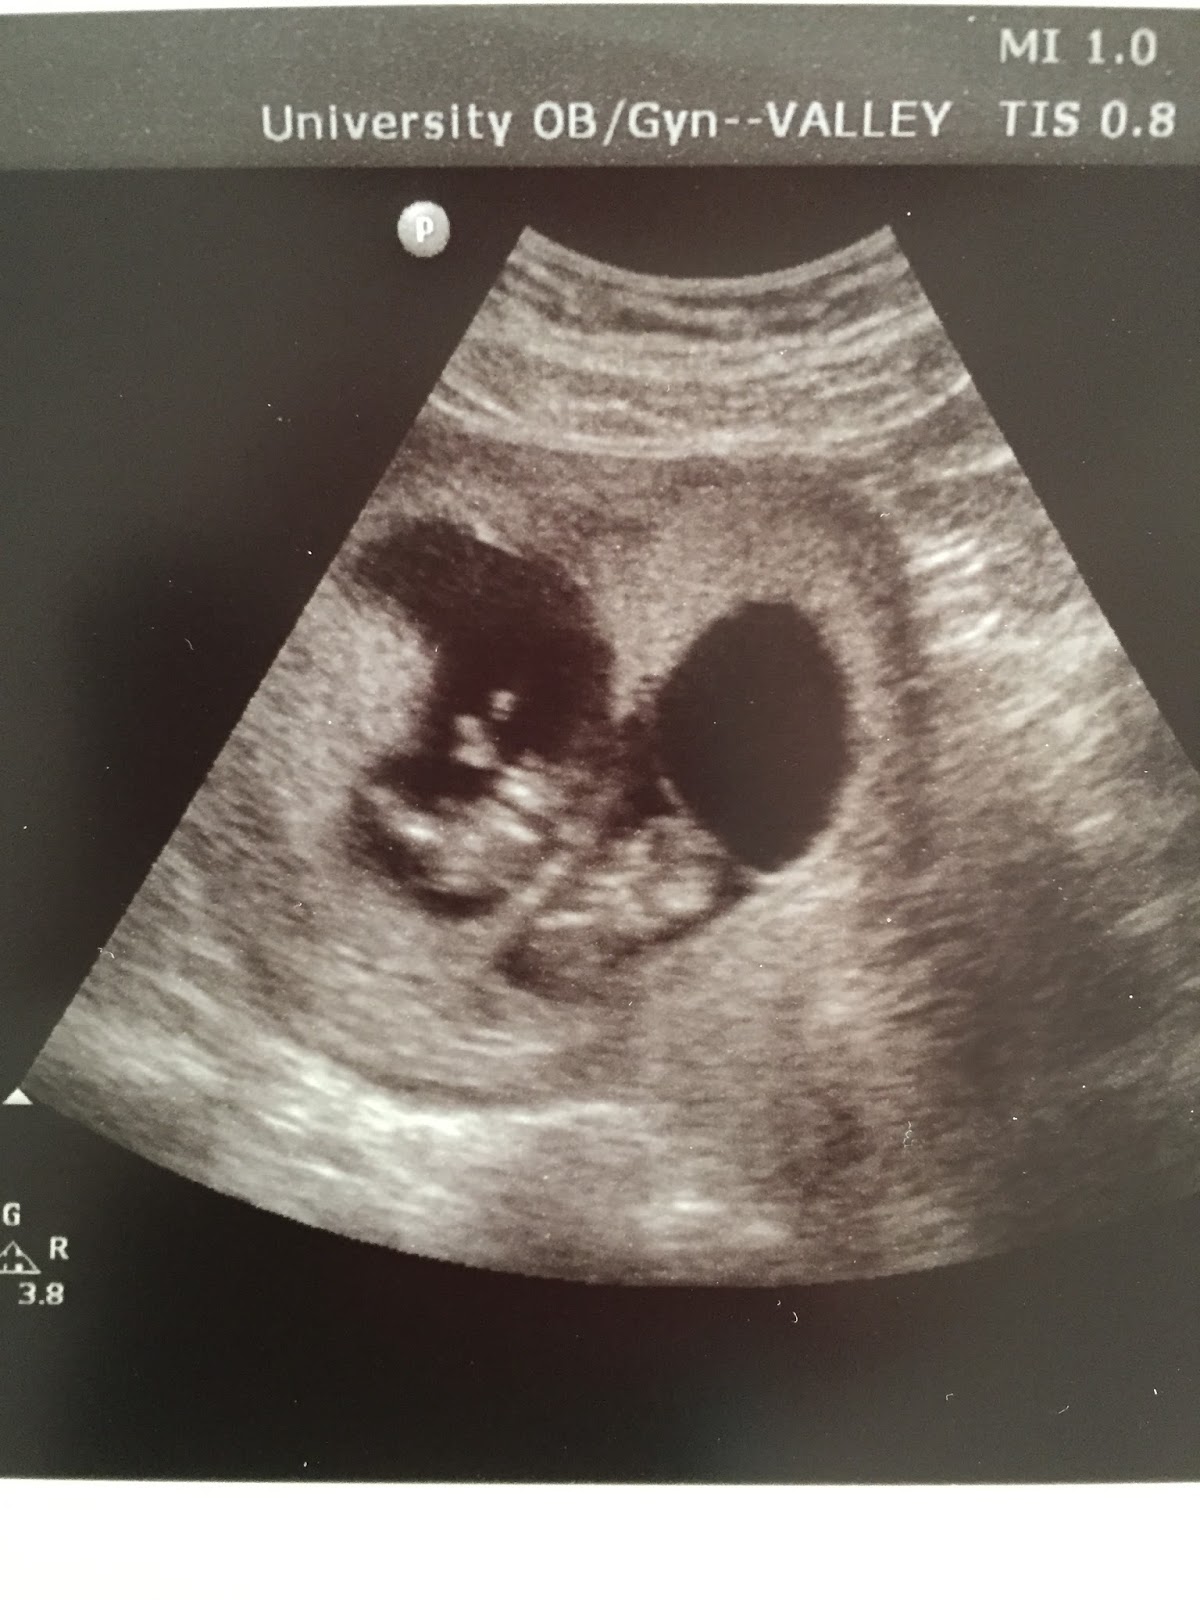

At 7 weeks pregnant (March 24), they check for strong heartbeats via ultrasound. They also check to see how many babies. We were praying for one, and so excited to see TWO strong heartbeats. It was amazing. We were both pretty emotional. TWINS! They put my due date as Nov 8th, being 40 weeks. But with twins, we will probably deliver between 36-37 weeks, which will be the middle of October.

Getting to see our little peanuts (above) made everything worth it! I loved getting to go to the Dr so often and see them and their beating hearts. Hearing a baby's heartbeat is the best sound in the world!!!

I "graduated" from my Reproductive Endo Dr. around 10 weeks and saw my "real" OB for the first time. More ultrasound pics of the babies. Always so fun. It is amazing to watch them grow in such a short amount of time! I love it!

We also had another ultrasound of the babies that week. Thanks to Scott's amazing Labor and Delivery staff, they told me to come in whenever I wanted to check on the babies. I have taken them up on their offer several times! Especially in the beginning when things are still risky. It is so fun to see them in there wiggling around!